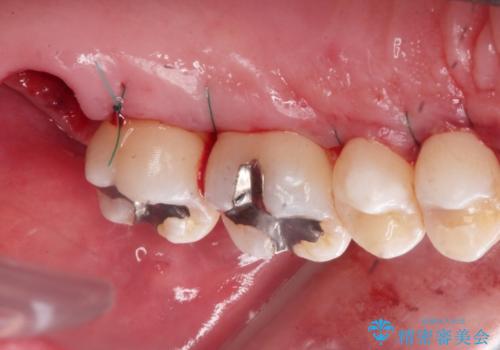

3. 縁下歯石のクリーニングの治療後